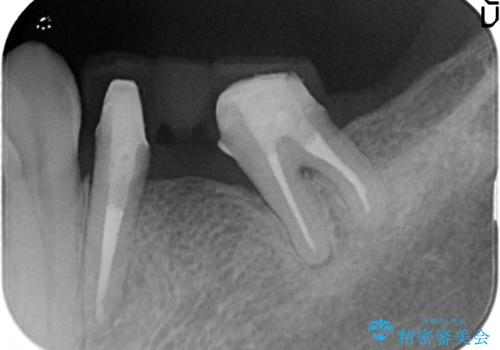

金属のかぶせ物をセラミックへ 根管治療からの再治療

左側の上下の奥歯に適合が悪く、レントゲン上でも根の治療が必要なところがありました。

再治療を行いました。

根管治療からの再治療を行ったことにより、治療期間が多少長くなりましたが、今後再治療の必要性があまりないような、精度の高い治療ができました。